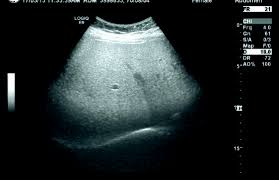

- 초음파 검사: 간의 상태를 초음파를 통해 직접 확인합니다.